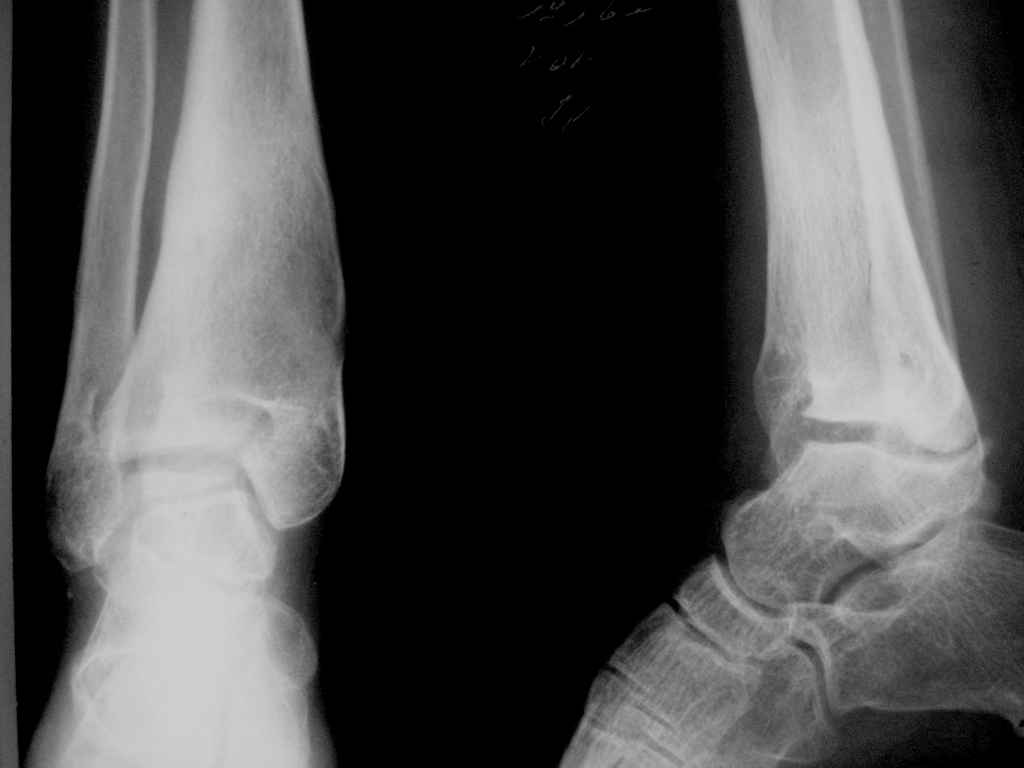

Девушка 17 лет: боли в голеностопном суставе,ограничение движений в суставе,укорочение голени,хромота

Из анамнеза в раннем детском возрасте перенесла гематогенный остеомиелит дистального отдела большеберцовой кости - зона роста частично закрылась сформировалась варусная деформация голеностопного сустава + укорочение костей голени на 6 см Произведена корригирующе-удлиняющая остеотомия сначала большеберцовой,затем малоберцовой костей, устранена деформация, ликвидировано укорочение. С возрастом наросло укорочение до 3 см,клинически умеренная вальгусная деформация голеностопного сустава. Объём движений в суставе в пределах 15 град. Отмечает переодически болевой синдром, после осевой перегрузки,пользуется обувью с компенсацией, ортезом на голеностопный сустав

Вопрос: есть ли показания для оперативного лечения: артропластика? артродез? голеностопного сустава. Какие мысли,коллеги?